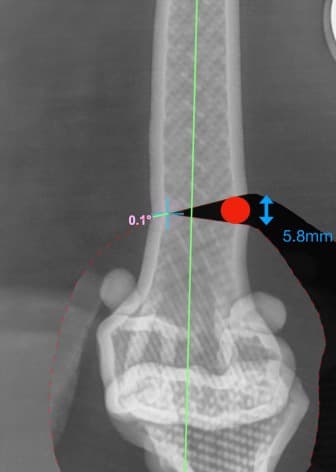

정형외과 전공의 수의사가 직접 수술합니다.

02C-arm을 통해서 좀 더 섬세한 정형외과 수술을 진행하고, 본원에서는 외과적 침습을 최소화 하는 중재적 시술 (기관 협착, 동맥관개존증(PDA), SUB 등)을 진행하고 있습니다.

13수술 중 골절 상태 혹은 이식물 적용 후 상태 등 육안으로 명확히 확인하기 힘든 상태를 X-ray 확인하여 정확한 수술 결과를 만들어 내는 것이 가능